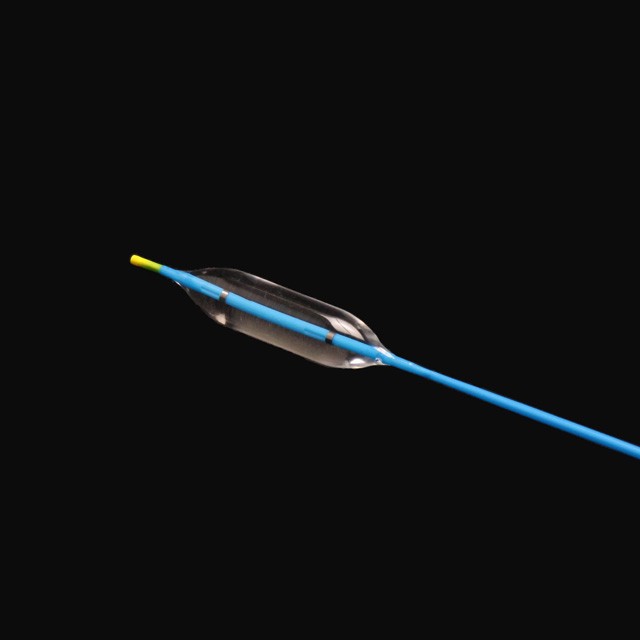

● idoneam adultis et adolescentes in DIATRUM operationem digestivorum tractu stricture sub endoscopes .

● in Balloon potest esse gradual auctus ad tres distincta diametri sub propria pressura, providente multo magis choice pro medicis .

● radiopaque venalicium in utroque fines de Balloon potest providere precise positioning sub X Ray {{I}}